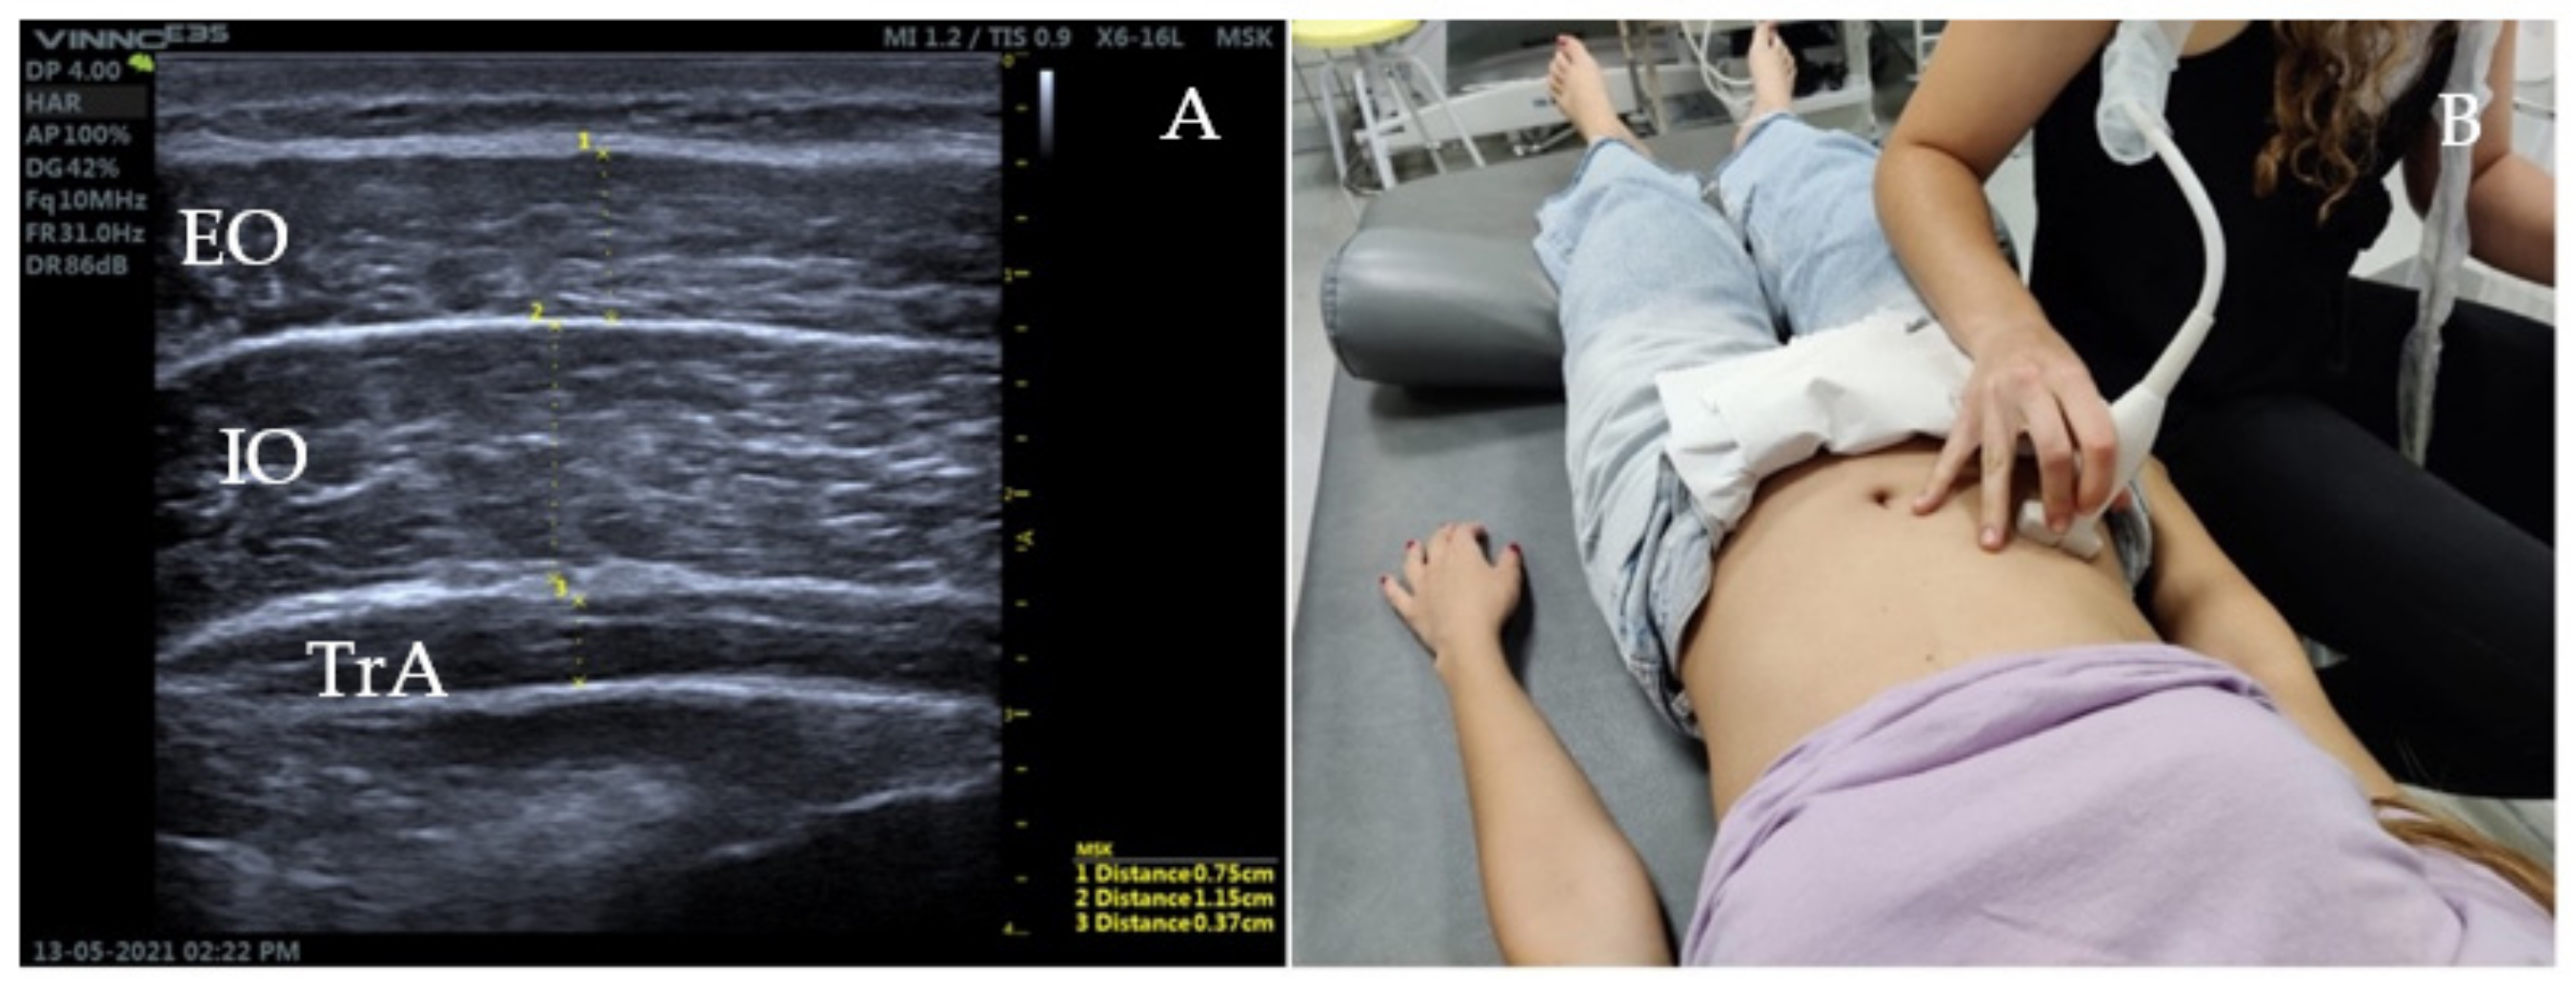

2.5. Ultrasound Measurement of the Abdominal Wall